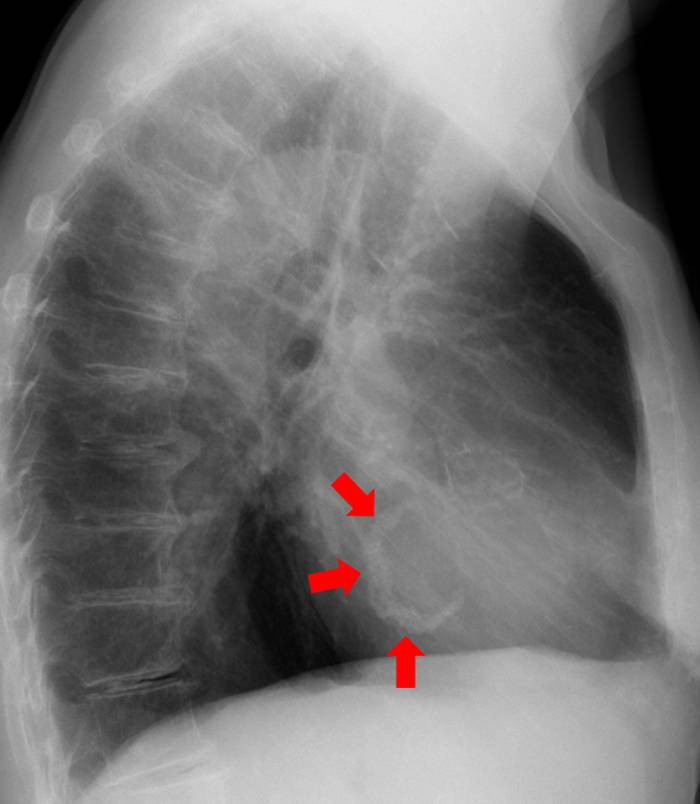

Trichterbrust: Dorsalverlagerung des Herzens (Thorax pa und links seitlich) |

Verkalktes Vorderwandaneurysma (Pfeile; Thorax links seitlich) |